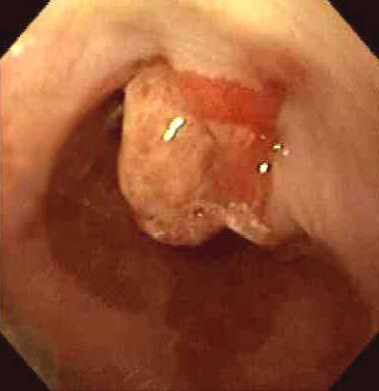

| This is the view of the lower esophagus seen on endoscopy. Note the areas of dark red friable mucosa representing Barrett esophagus. Note the polypoid mass which on biopsy proved to be a moderately differentiated adenocarcinoma. This patient had a 30 year history of poorly controlled gastroesophageal reflux disease. |